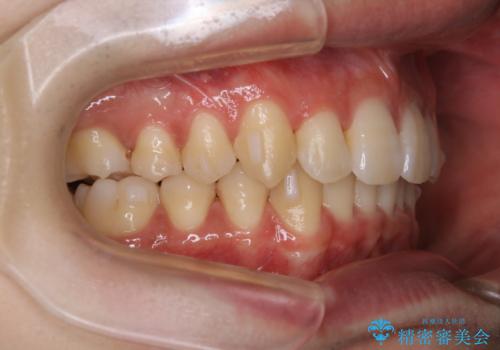

インビザライン:前歯のがたつきと噛み合わせの治療

- 前歯のがたつきが気になるとご相談にいらした方です。左の奥歯の噛み合わせのズレも認められたため、インビザライン治療にて改善しました。

主訴である前歯のガタつきだけでなく、奥歯の噛み合わせからしっかり治療したため、治療期間が長めとなりました。患者様ご本人としては治療の途中で一時的にモチベーションが下がったこともあったようですが、最後まで頑張って続けて頂けたことで噛み合わせ及び見た目の改善を行うことが出来ました。